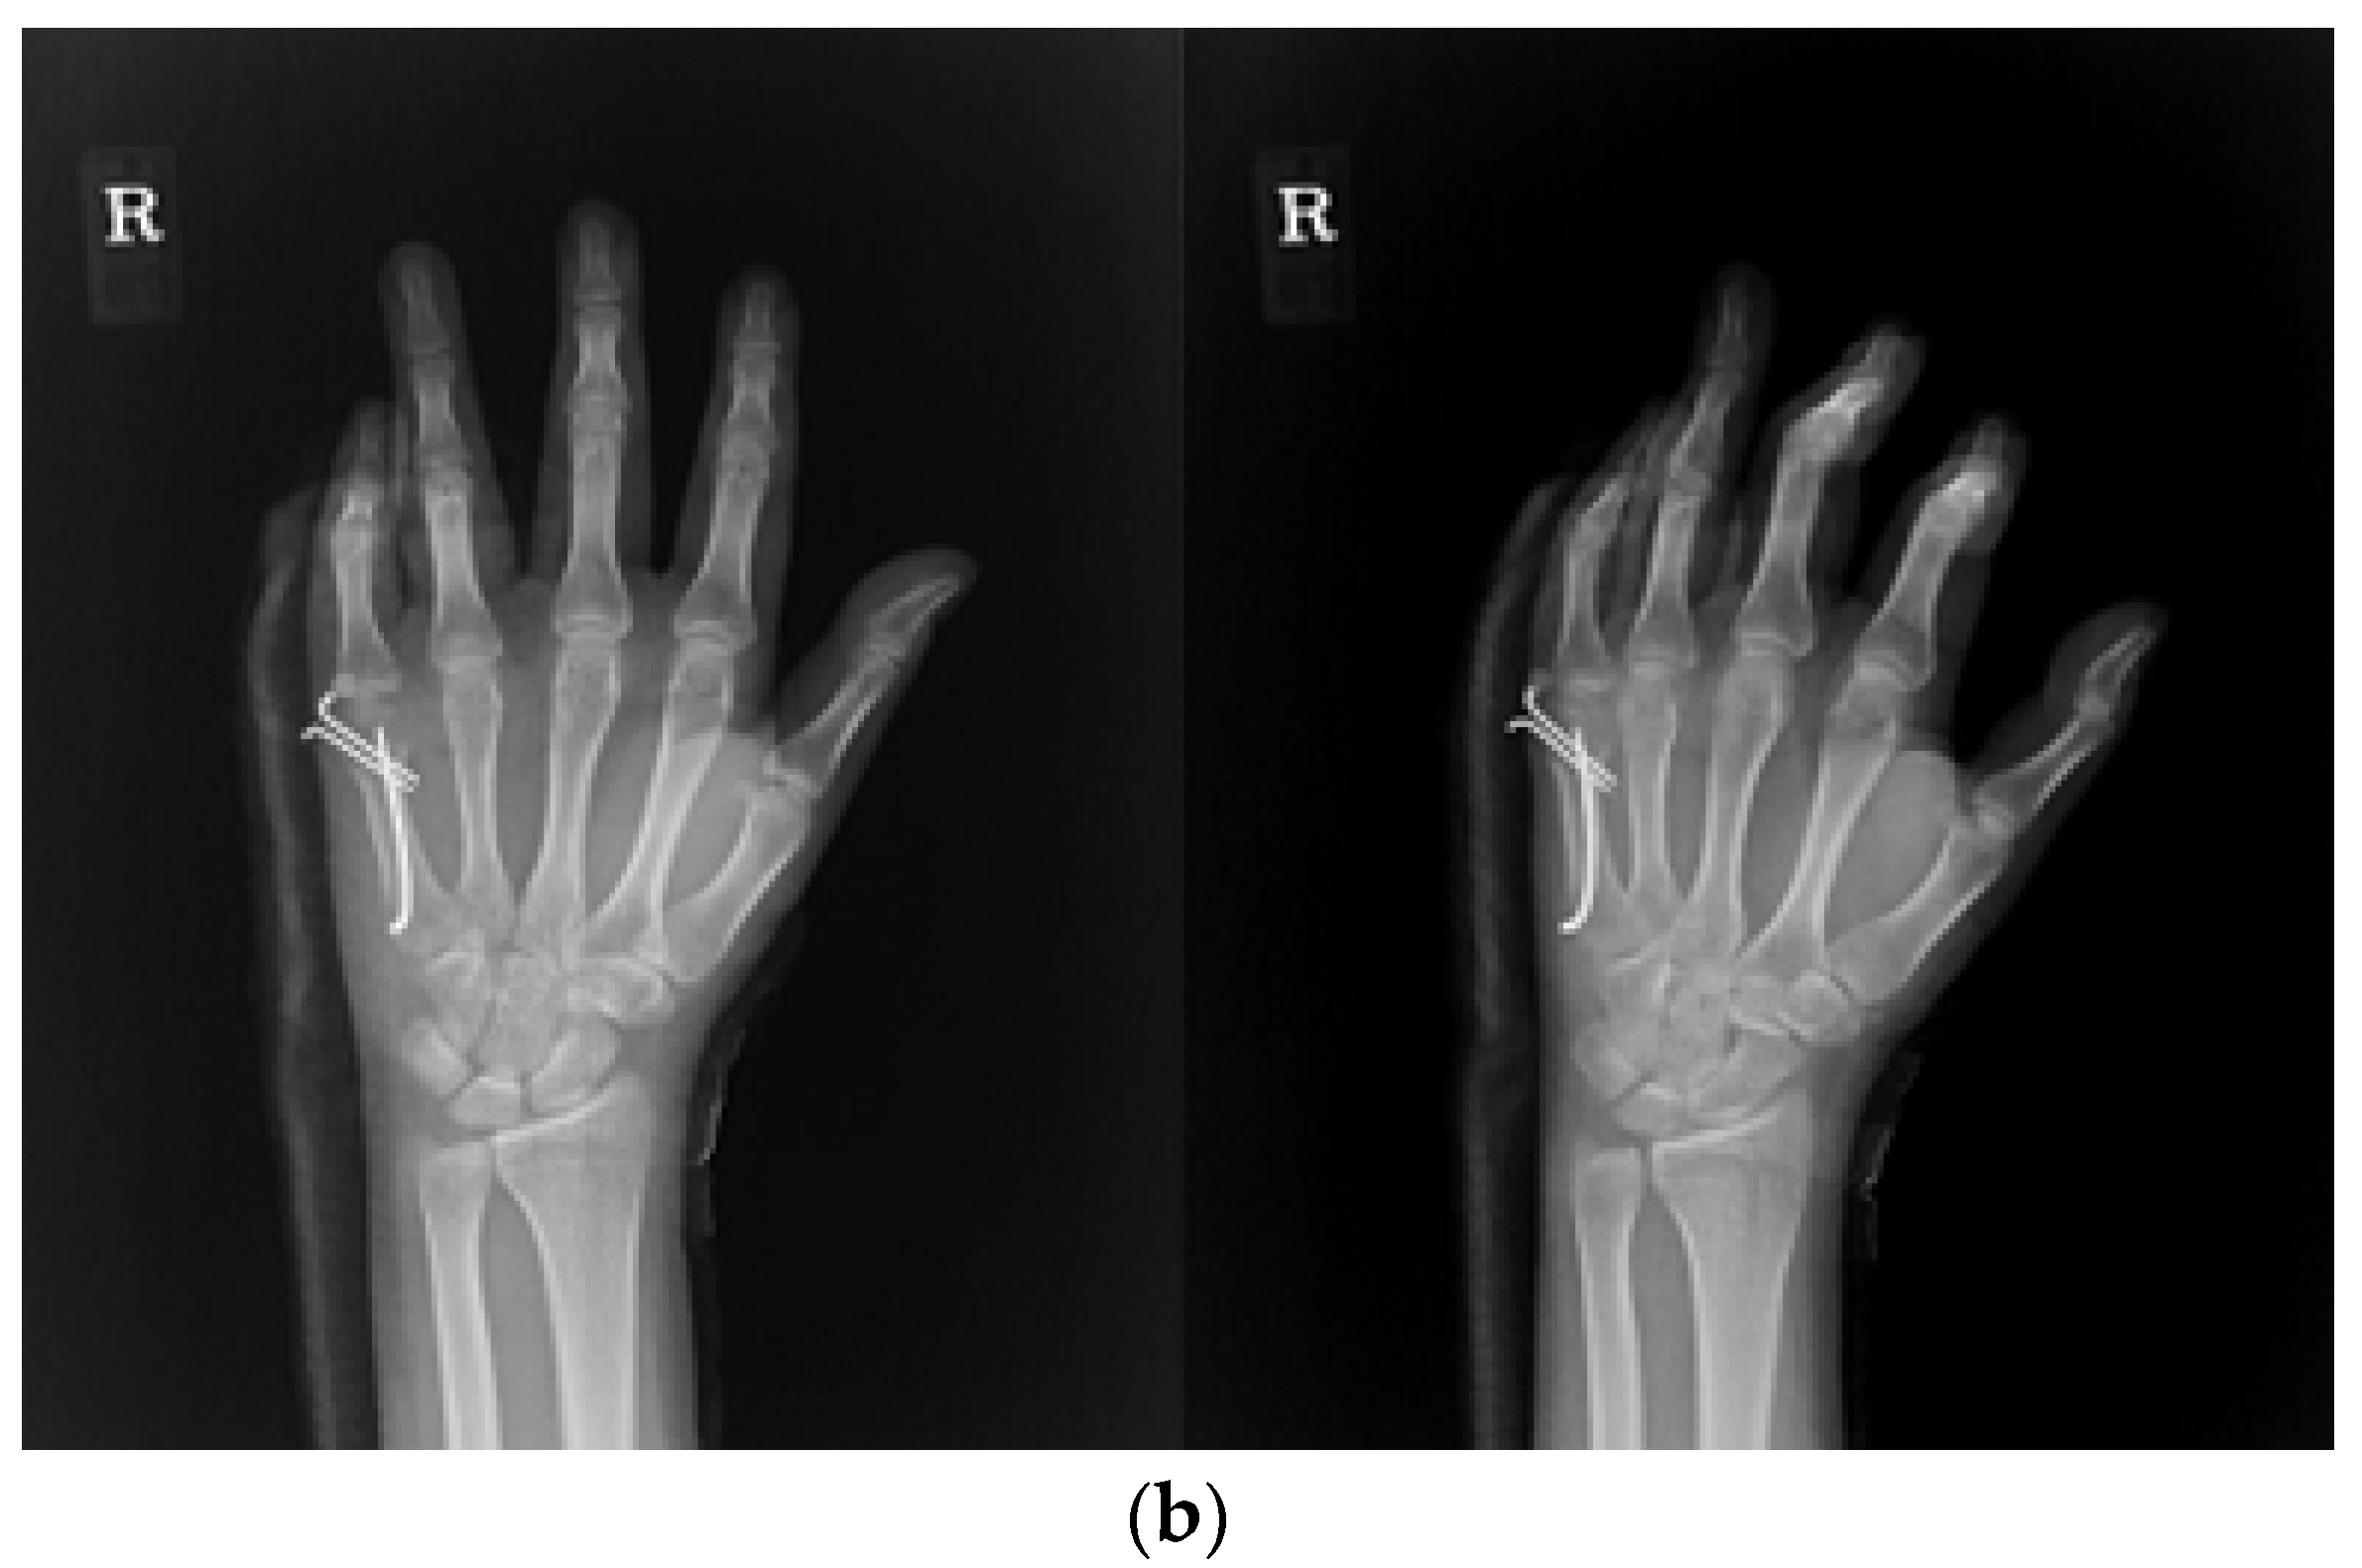

The combined method involved the placement of an intramedullary pin followed by parallel K-wire fixation. Initially, an intramedullary nail was inserted into the metacarpal bone to stabilize the fracture, typically through the base. Following intramedullary pinning, K-wires were placed across the distal part of the intramedullary nail, and the pin was inserted halfway through the dorsal aspect of the nail, touching the nail and making an additional accurate reduction possible. Another pin was inserted on the volar aspect of the nail (Figure 3a,b).

Figure 3.

(a) Radiograph of an 18-year-old male patient with displaced little-finger metacarpal neck fracture. (b) Radiograph of a 16-year-old male patient who underwent the IPKP method using one intramedullary nail and two additional K-wires.